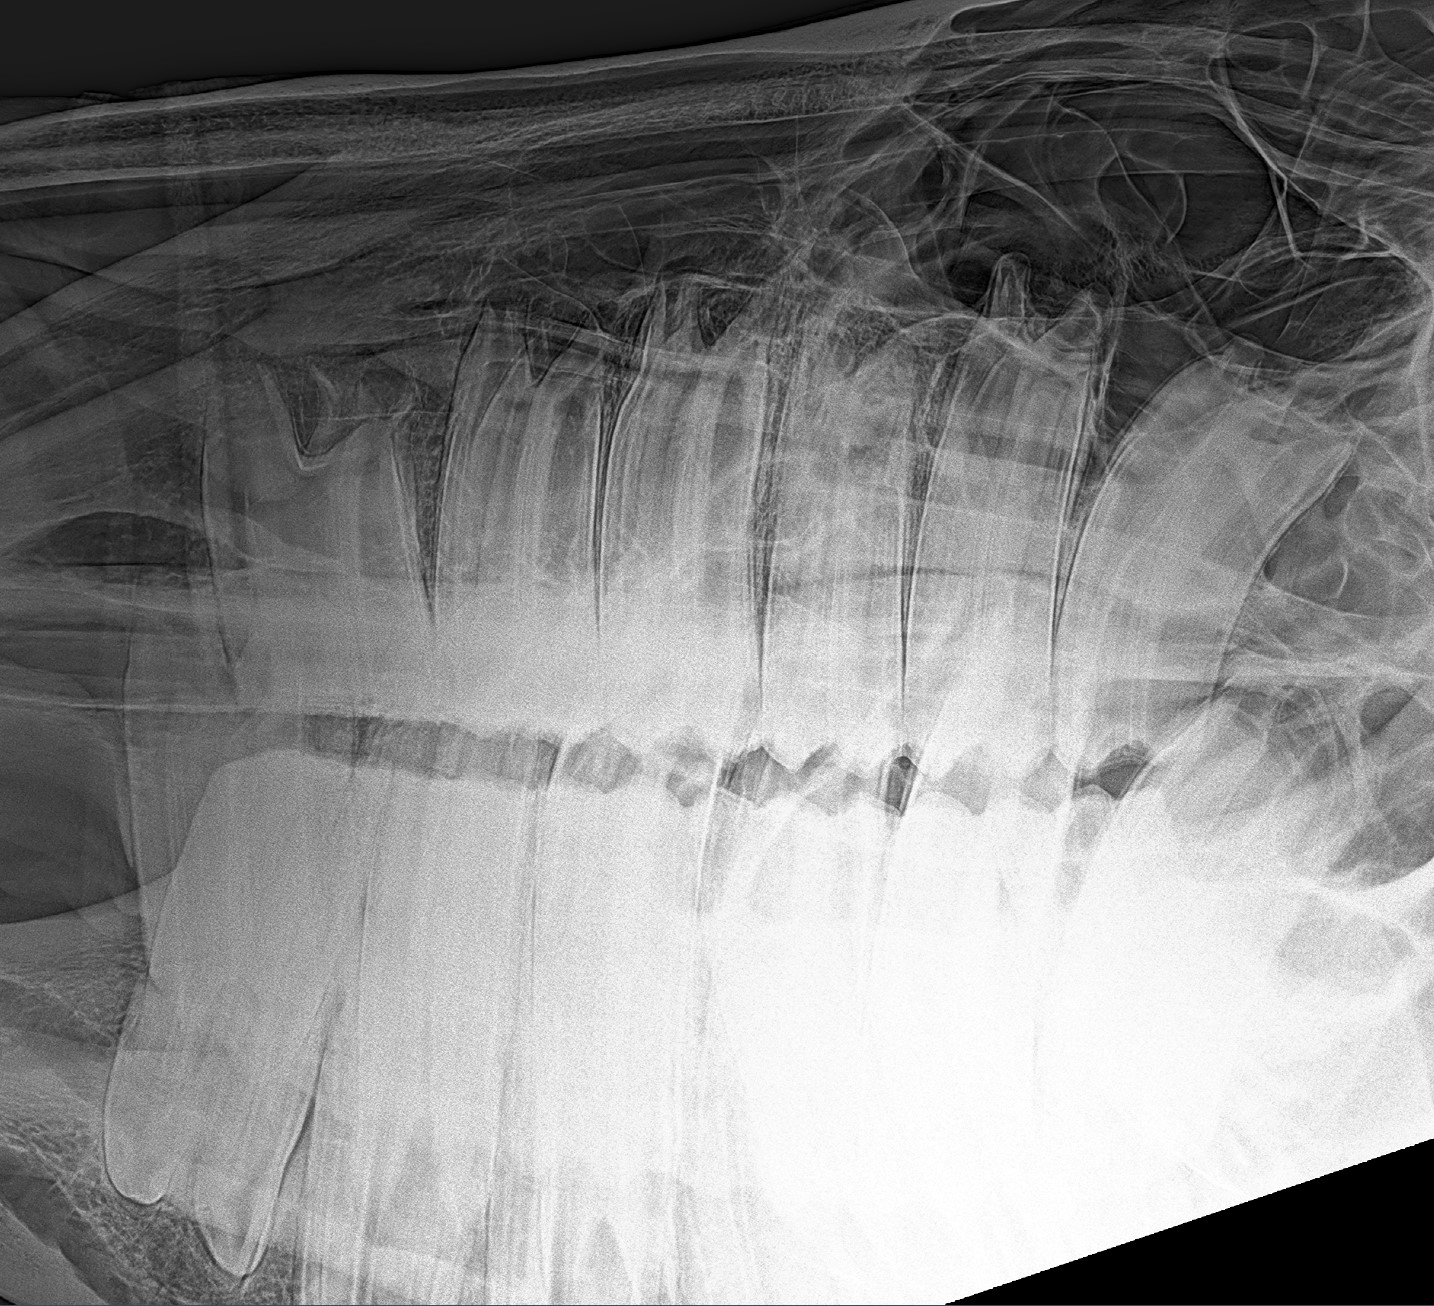

Rx 8-jährig

Backenzähne Oberkiefer 8-jährig